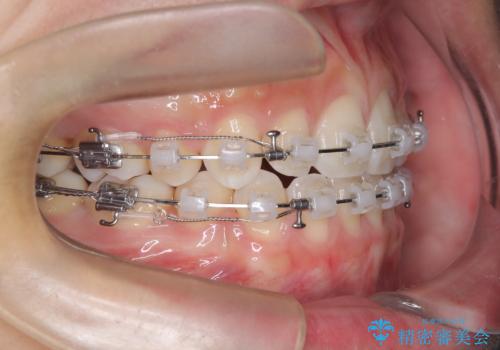

- 治療計画

上下左右の第一小臼歯を抜歯し、クリアブラケット(白い装置)とメタルワイヤーを使用して矯正を開始。初期には犬歯のアーチ内への整列を優先し、中盤からは前歯と奥歯の咬合関係の調整を進めました。審美性に優れた装置を使用したことで、治療中も目立ちにくく、見た目へのストレスが少ない点も評価されています。全体の治療は1年半で完了し、見た目・噛み合わせともに大きく改善。患者本人も「短期間でここまで変わるとは思わなかった」と満足されていました。